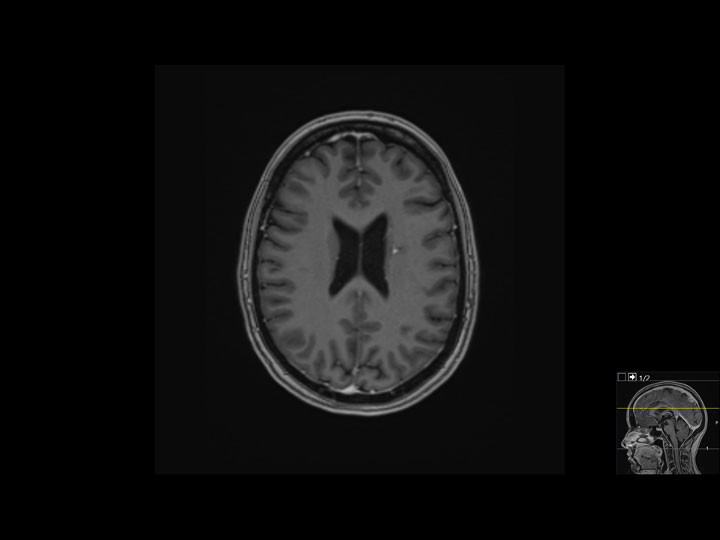

After discharge, the patient's mental health recovered and she returned to her normal weight. Following initial systemic therapy, which also included carboplatin and bevacizumab, she received intravenous pembrolizumab and pemetrexed every three weeks for a total of two years. She initially remembered little of what she had gone through, but subsequently expressed a need to process and understand her experience, and her memories have gradually resurfaced in 'flashbacks'. The topic of prognosis has been raised in several consultations, with the patient asking if she is healthy now. We informed her that the absence of signs of relapse four years after symptom onset and two years after her treatment was paused gives hope for a long-term positive outcome. Imaging shows only minor residual changes (Figure 3). The patient now lives in her own flat with her child and is looking for work. Here functional status is 0 (normal functioning).